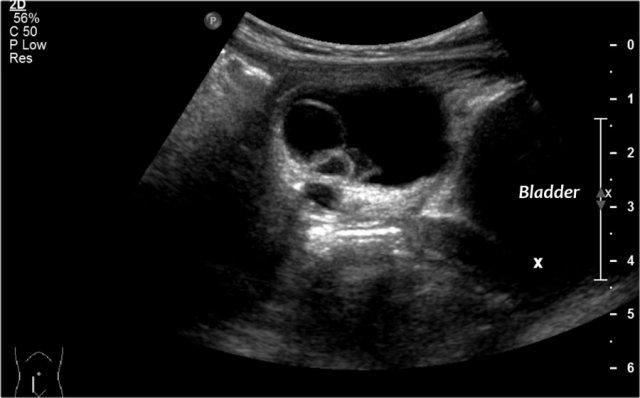

Xảo ảnh gương (mirror artifact) của bàng quang có thể giả dạng một khối u buồng trứng dạng nang.

Khi còn nghi ngờ, siêu âm lại sau khi bệnh nhân đi tiểu hết sẽ giải quyết được vấn đề này.